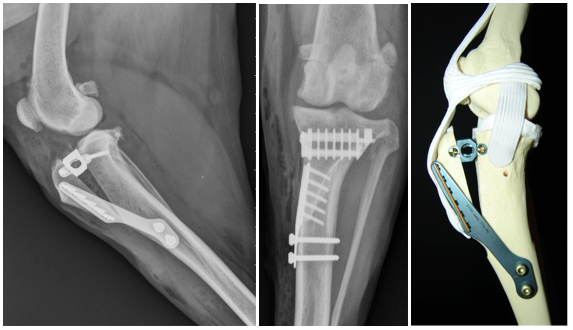

PGR patella groeve raplacement.

TTA                                         TPLO                                     CCWO

3DHIP

behandeling jonge honden met Heupdysplasie